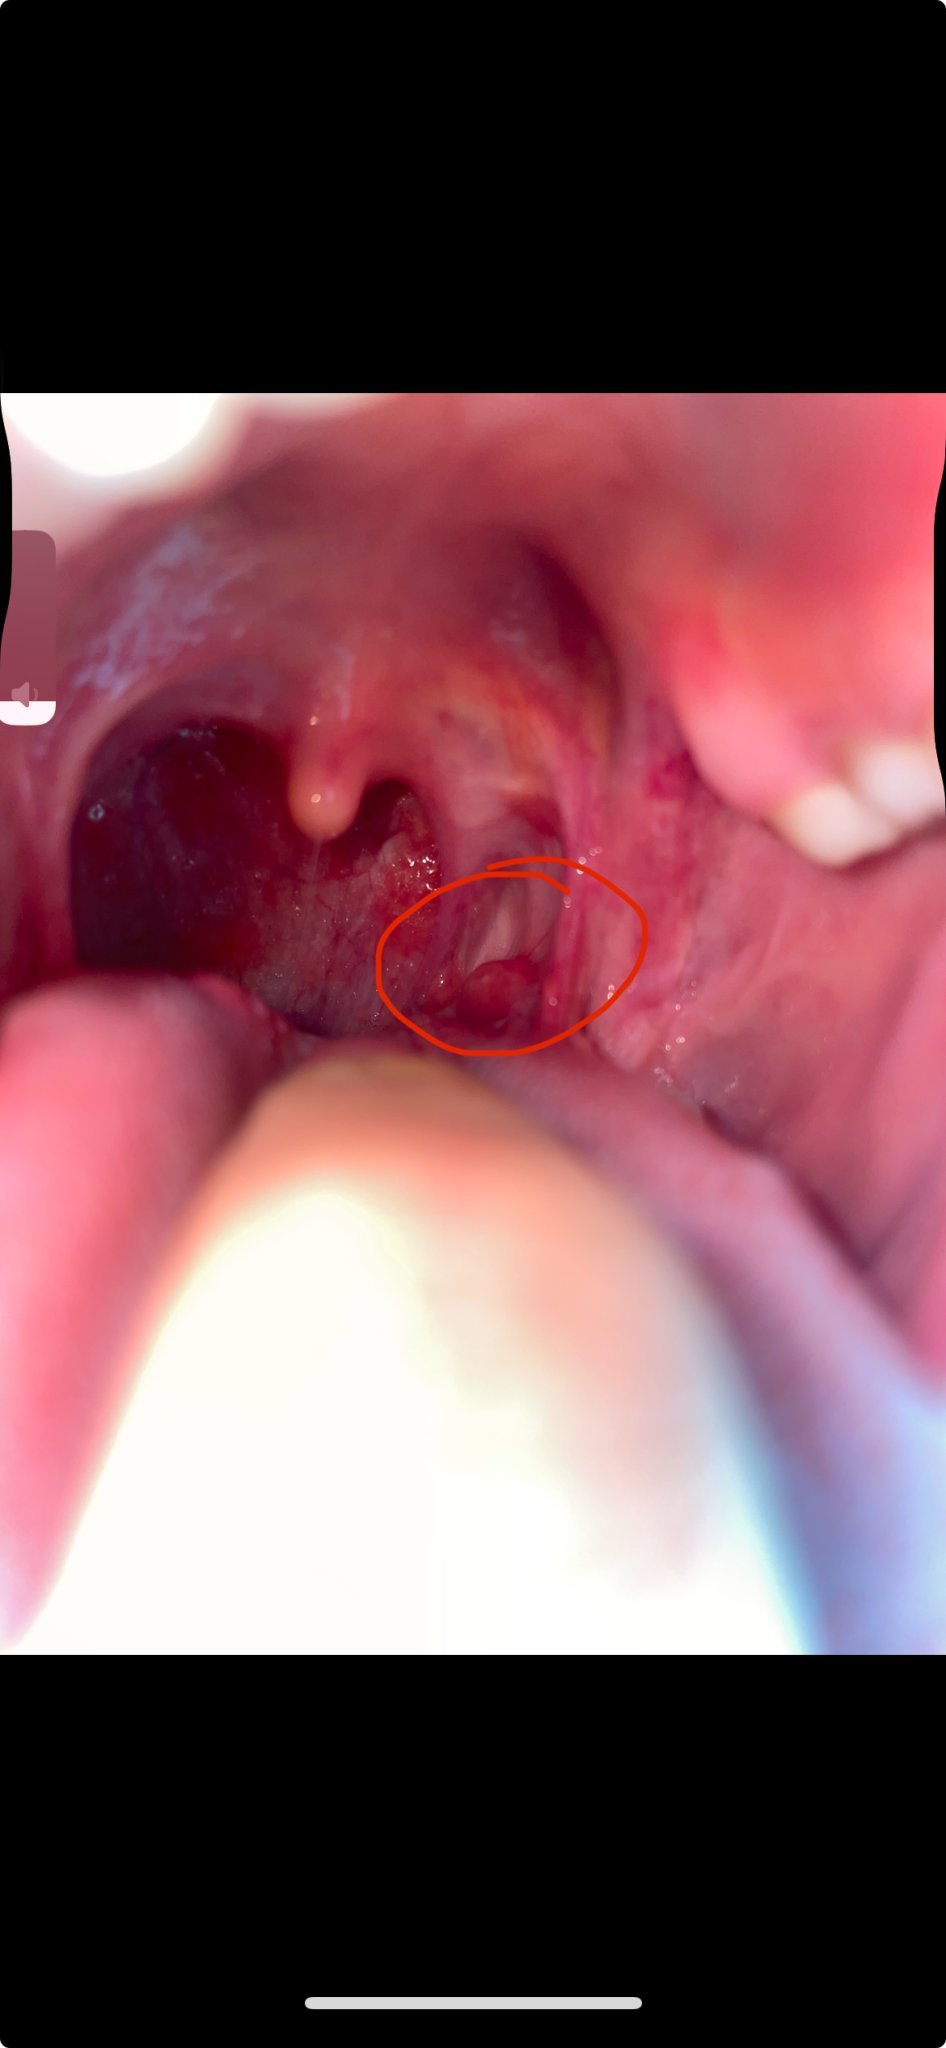

Здравейте, изключително съм притеснена и не знаех къде вече да пиша. Миналата седмица усетих дразнене и нещо като заседнало чуждо тяло в гърлото, посетих УНГ и ми каза хроничен Фарингит. Изписа ми лекарства и до тук добре. Обаче болката не минаваше а даже се появи и в ухото, днес вече забелязах и тези две топчета, четох какви ли не ужасии в интернет и в момента съм страшно притеснена. Някоя от вас знае ли какво може да бъде.

Благодаря Ви предварително!

Ами,това е фарингита, не се плашете не е страшен. При мен много помагаха таблетки за смучене Cetebe с вит С и цинк, веднага намаля възпалението и болката. Аз ги купувах от Германия обаче, при нас ги продават на малко места,защъто никой не ги купувал. Не знам защо лекарите изписват само глупости без ефект. Ангал спрей трепе бактериите, а отвара от дафинов лист за гаргара е уникално.

На мен след фарингита ми остана бяло топче, което го лекувах две години с гаргара със запарка от салвия. Понякога са упорити, но след острия период после няма болка.